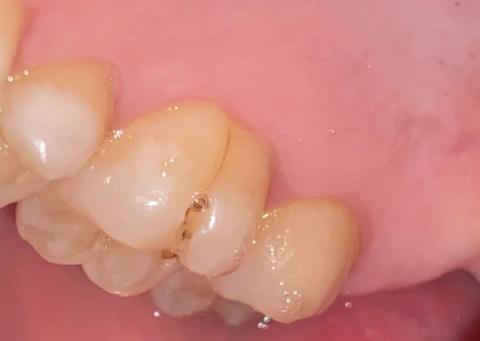

The image shows posterior teeth (side view) with a small dark lesion located between two adjacent teeth. The enamel surface is mostly intact, but there is localized discoloration and a pinpoint cavity, consistent with early interproximal dental caries.

Affected Tooth

Small dark spot at the contact area

Early enamel breakdown

No large cavitation visible

High plaque-retention zone between teeth

Enamel appears intact

No visible cavitation

Risk of secondary decay if untreated